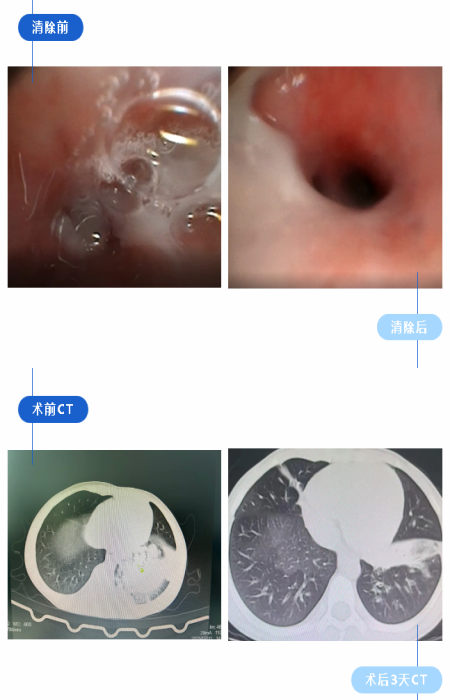

该患儿入院前已反复咳嗽一月余,胸部CT显示明显肺实变,提示存在严重肺部感染及气道阻塞可能,常规抗感染及对症治疗效果不佳。经儿科专家团队全面评估,结合影像学与临床表现,决定实施电子支气管镜下肺泡灌洗术。手术过程顺利,操作精准,通过支气管镜直视下清除气道分泌物并完成肺泡灌洗,有效促进了肺部炎症的消退与实变病灶的吸收。术后患儿咳嗽、咳痰症状明显减轻,肺部啰音显著减少,术后第3天复查胸部CT显示肺实变吸收约80%,呼吸功能明显改善,家长对治疗效果高度认可。